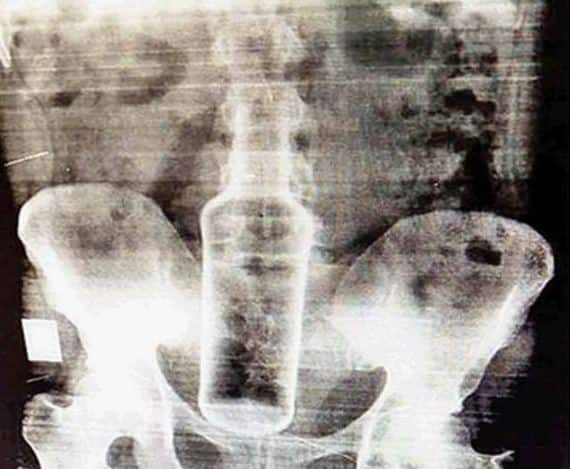

ਚੰਡੀਗੜ੍ਹ: ਪੀਜੀਆਈ 'ਚ ਡਾਕਟਰਾਂ ਦੀ ਟੀਮ ਨੇ 22 ਸਾਲਾ ਨੌਜਵਾਨ ਦੇ ਪ੍ਰਾਈਵੇਟ ਪਾਰਟ ਵਿੱਚੋਂ ਕੱਚ ਦੀ ਬੋਤਲ ਕੱਢੀ ਹੈ। ਨੌਜਵਾਨ ਯੂਪੀ ਦੇ ਮੁਰਾਦਾਬਾਦ ਦਾ ਰਹਿਣ ਵਾਲਾ ਹੈ ਤੇ ਚੰਡੀਗੜ੍ਹ 'ਚ ਮੌਲੀਜਾਗਰਾਂ 'ਚ ਆਪਣੀ ਮਾਂ ਨੂੰ ਮਿਲਣ ਆਇਆ ਸੀ। ਉਹ ਟ੍ਰੇਨ 'ਚ ਮੁਰਾਦਾਬਾਦ ਤੋਂ ਚੰਡੀਗੜ੍ਹ ਆਇਆ। ਇਸ ਦੌਰਾਨ ਉਸ ਨੇ ਇੱਕ ਹੋਰ ਵਿਅਕਤੀ ਨਾਲ ਸਫਰ 'ਚ ਸ਼ਰਾਬ ਪੀਤੀ। ਨਸ਼ੇ 'ਚ ਧੁੱਤ ਹੋਏ ਵਿਅਕਤੀ ਨੇ ਉਸ ਦੇ ਪ੍ਰਾਈਵੇਟ ਪਾਰਟ 'ਚ ਕੱਚ ਦੀ ਬੋਤਲ ਪਾ ਦਿੱਤੀ ਸੀ। ਇਸ ਦਾ ਖੁਲਾਸਾ ਉਦੋਂ ਹੋਇਆ ਜਦੋਂ ਘਰ ਆ ਉਸ ਦੇ ਢਿੱਡ 'ਚ ਦਰਦ ਹੋਇਆ। ਉਸ ਨੂੰ ਇਲਾਜ ਲਈ ਪੰਚਕੂਲਾ ਦੇ ਸੈਕਟਰ 6 ਦੇ ਸਿਵਲ ਹਸਪਤਾਲ ਭਰਤੀ ਕੀਤਾ ਗਿਆ। ਜਿੱਥੇ ਉਸ ਦੀ ਹਾਲਤ ਨੂੰ ਗੰਭੀਰ ਵੇਖਦੇ ਹੋਏ, ਉਸ ਨੂੰ ਪੀਜੀਆਈ ਰੈਫਰ ਕਰ ਦਿੱਤਾ ਗਿਆ। ਇੱਥੇ ਉਸ ਦੇ ਪ੍ਰਾਈਵੇਟ ਪਾਰਟ ਤੇ ਢਿੱਡ ਦਾ ਐਕਸ-ਰੇਅ ਕੀਤਾ ਗਿਆ ਜਿਸ 'ਚ ਪਤਾ ਲੱਗਿਆ ਕਿ ਉਸ ਦੇ ਪ੍ਰਾਈਵੇਟ ਪਾਰਟ 'ਚ ਕੱਚ ਦੀ ਬੋਤਲ ਹੈ। ਇਸ ਤੋਂ ਬਾਅਦ ਅਪ੍ਰੇਸ਼ਨ ਕਰ ਬੋਤਲ ਨੂੰ ਕੱਢਿਆ ਗਿਆ। ਚੰਡੀਗੜ੍ਹ ਜੀਆਰਪੀ ਦੇ ਐਸਐਚਓ ਨਰੇਸ਼ ਕੁਮਾਰ ਨੇ ਦੱਸਿਆ ਕਿ ਨੌਜਵਾਨ ਦੇ ਬਿਆਨਾਂ ਦੇ ਅਧਾਰ ’ਤੇ ਅਣਪਛਾਤੇ ਵਿਅਕਤੀ ਖ਼ਿਲਾਫ਼ ਕੇਸ ਦਰਜ ਕੀਤਾ ਗਿਆ ਹੈ। ਮੁਲਜ਼ਮ ਦੀ ਭਾਲ ਲਈ ਮੁਰਾਦਾਬਾਦ, ਅੰਬਾਲਾ ਤੇ ਚੰਡੀਗੜ੍ਹ ਰੇਲਵੇ ਸਟੇਸ਼ਨਾਂ ਦੇ ਸੀਸੀਟੀਵੀ ਕੈਮਰਿਆਂ ਦੀ ਭਾਲ ਕੀਤੀ ਜਾ ਰਹੀ ਹੈ। ਚੰਡੀਗੜ੍ਹ ਜੀਆਰਪੀ ਨੇ ਜ਼ੀਰੋ ਐਫਆਈਆਰ ਦਰਜ ਕਰਕੇ ਕੇਸ ਨੂੰ ਮੁਰਾਦਾਬਾਦ ਪੁਲਿਸ ਨੂੰ ਭੇਜ ਦਿੱਤਾ ਹੈ। ਇਸ ਮਾਮਲੇ 'ਚ ਉੱਤਰ ਪ੍ਰਦੇਸ਼ ਪੁਲਿਸ ਨੇ ਜ਼ੀਰੋ ਐਫਆਈਆਰ ਦੇ ਆਧਾਰ 'ਤੇ ਮਾਮਲਾ ਦਰਜ ਕਰਕੇ ਕਾਰਵਾਈ ਸ਼ੁਰੂ ਕਰ ਦਿੱਤੀ ਹੈ।